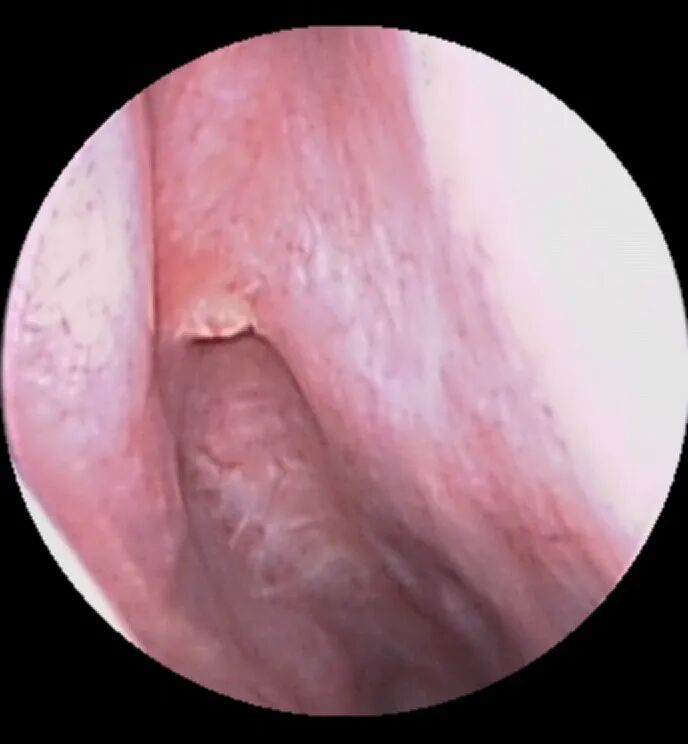

2.下一步需要使用双极电凝进行局部电凝止血,也就是在出血部位的粘膜进行电刺激使粘膜形成血栓封闭出血动脉,达到控制出血的目的,如下图所示:

图:予电凝烧灼